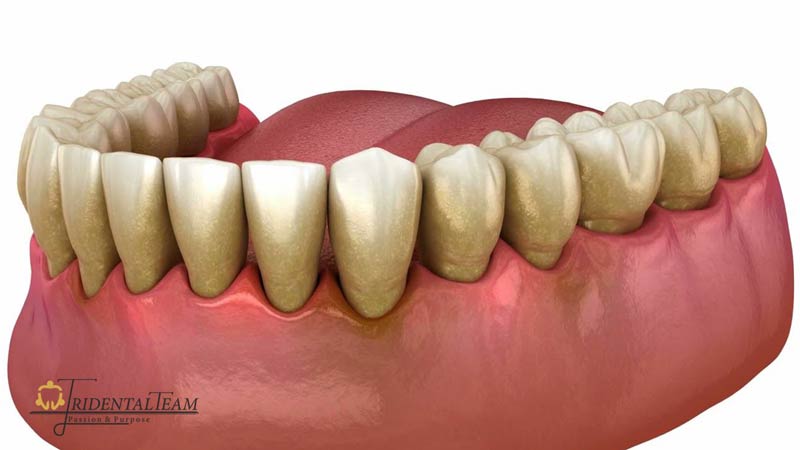

تحلیل لثه یا عقب رفتن لثه، به حالتی گفته می شود که بافت لثه به تدریج از روی دندان ها عقب می رود و باعث نمایان شدن سطح ریشه دندان می شود. این وضعیت نه تنها ظاهر لبخند را تحت تأثیر قرار می دهد، بلکه می تواند موجب حساسیت دندان، افزایش خطر پوسیدگی ریشه و حتی لق شدن دندان ها شود. تحلیل لثه معمولاً روندی تدریجی دارد و بسیاری از افراد تا زمان پیشرفت قابل توجه آن، متوجه این مشکل نمی شوند.

دلایل مختلفی می توانند در بروز تحلیل لثه نقش داشته باشند. مهم ترین عامل، بیماری های لثه مانند ژنژیویت و پریودنتیت است که به واسطه تجمع پلاک های میکروبی در اطراف دندان ایجاد می شوند. همچنین مسواک زدن خشن، استفاده از مسواک با الیاف زبر، فشار بیش از حد هنگام مسواک زدن، ناهنجاری های دندانی، تغییرات هورمونی، سیگار کشیدن و عوامل ارثی نیز از دیگر علل شایع تحلیل لثه به شمار می روند. شناخت به موقع این عوامل و مراجعه به موقع به بهترین دندانپزشک تهران، نقش مهمی در جلوگیری از پیشرفت این مشکل دارد.

- عقب رفتن لثه و بلندتر به نظر رسیدن دندان ها

- مشاهده ریشه دندان